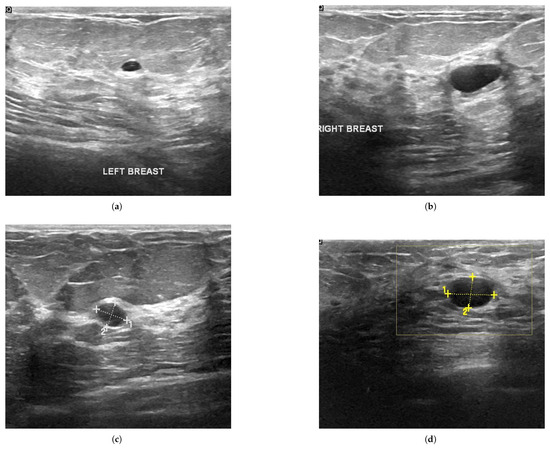

Moreover, this Special Issue will discuss how to integrate data from different imaging techniques (such as MRI, CT, PET, and ultrasound) to provide more comprehensive diagnostic information; to study the potential of multi-modal data fusion in improving the accuracy of disease detection and classification; and the application of AR and VR technologies in biomedical image analysis, particularly in surgical planning and educational training.